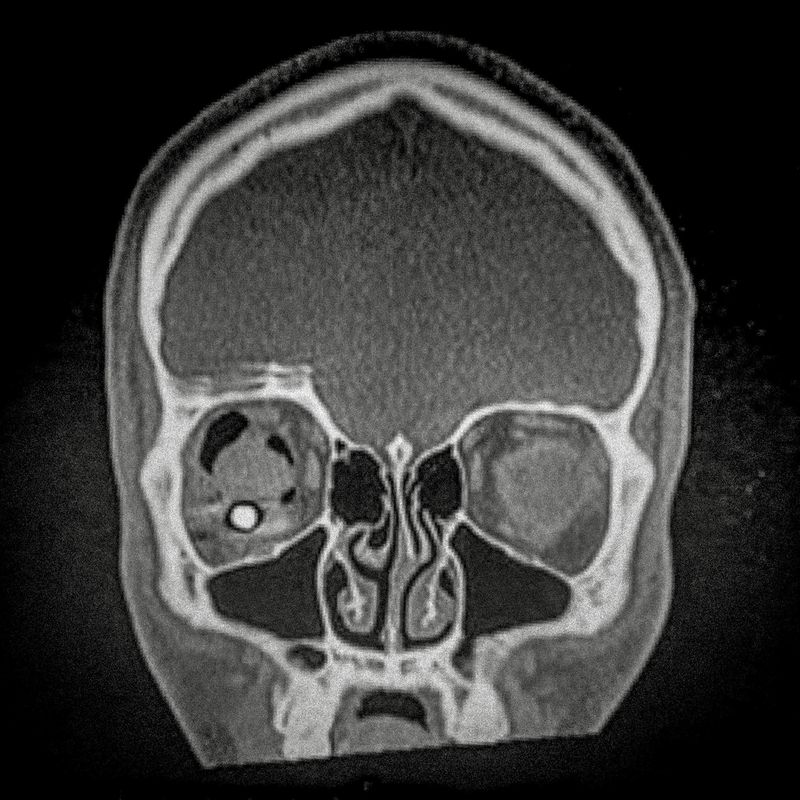

X-ray of Fabiola Campillai's face after she received a direct hit from a tear gas bomb fired by the carabineros chilean police, that caused her to lose both eyes.